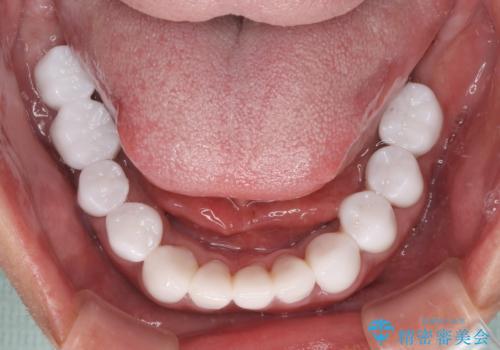

欠損と虫歯だらけの口の中 真っ白なセラミック治療

- 奥歯の欠損や、ボロボロになった歯を気にして来院された患者様です。

インプラントにより奥歯の咬み合わせが安定し、上顎前歯の歯肉ラインを調整するための骨外科処置により深く咬みこんでいた前歯部も負担のかからない咬み合わせに改善することができました。